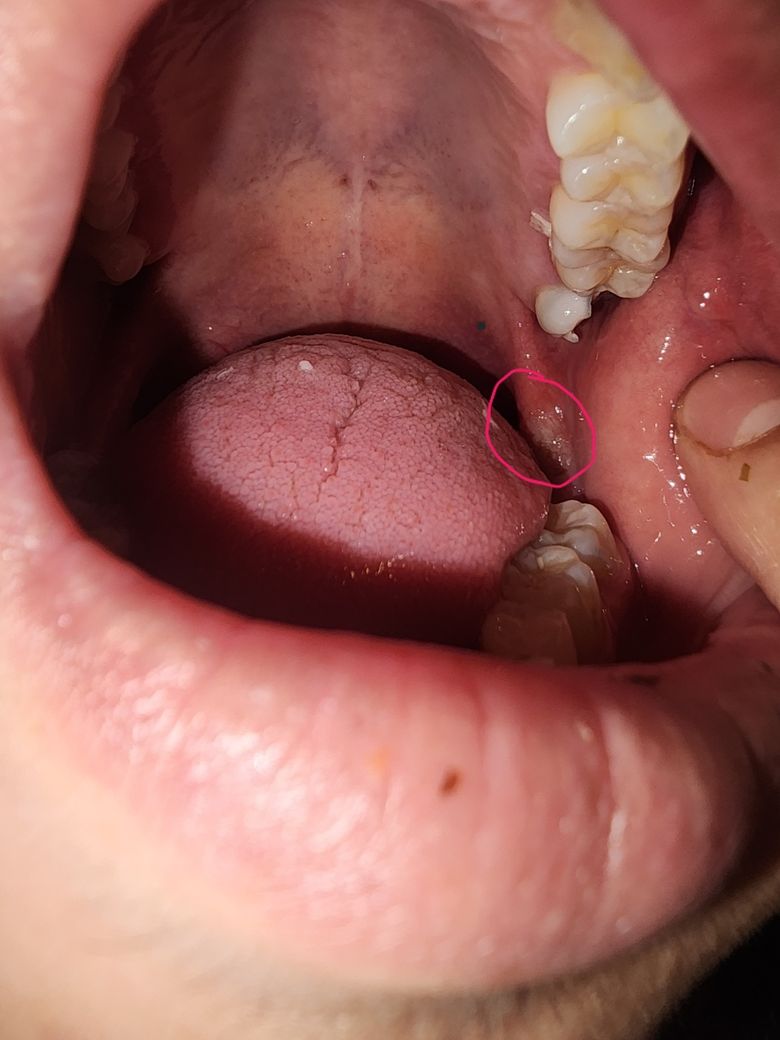

입안에 생긴게 뭐에요??!!급해요

입안에 뭔가 생겼는데 혹시 궤양일수도 있나요 ㅠㅠㅠㅠ살짝 딱딱한거같아요 아프고 따가워요 ㅠㅜ도와주세요 뭐라설명해야할지 모르겠어요 ㅠㅠㅠㅠㅠ

• 정확한 것은 x-ray 등의 사진 및 임상 검사를 해보아야겠지만 위쪽 사랑니로 인하여 연조직이 지속적으로 자극받아 생긴 것으로 보여집니다. 즉 사진 상에서 위에 보이는 사랑니가 해당 부위를 지속적으로 자극하고 있을 것으로 보여집니다.